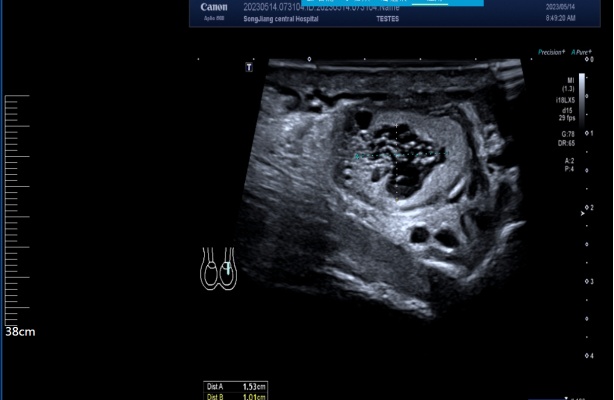

腹股沟斜疝超声图

“喂,吴主任吗,我这儿有位80岁老伯,他下体腹股沟出现巨大疝气,但他的情况很特殊,不太好上麻醉………”5月中旬的一天,接诊吴老伯的区中心医院普外科主任张俊华,第一时间联系了麻醉科主任吴德华。原来,老人因患有腹股沟斜疝已严重影响日常行走及生活,但10年前其做过心脏手术,目前心脏超声检查显示其整个心脏扩大,心脏收缩功能极度受损,甚至部分心脏肌肉无法正常收缩。如果麻醉方法和术中处理有任何的失误,都可能引发心脏收缩能力进一步下降,甚至出现严重心律失常以及心跳突然停止,威胁生命。不仅如此,老人还患有肾功能衰竭,这些都给手术麻醉带来不小的风险。